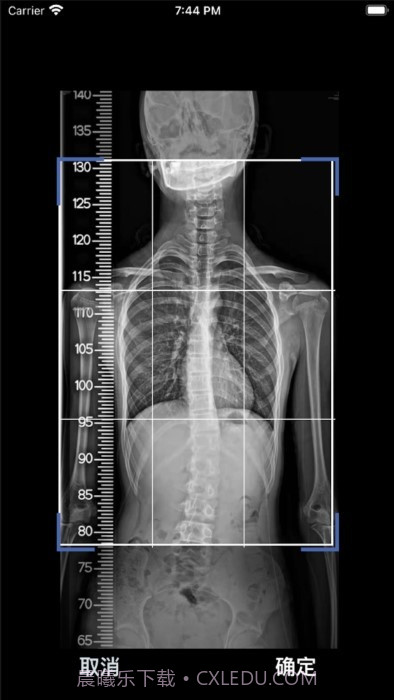

这款cobb角测量分析平台简直大概是医生和脊柱侧弯患者的福音!🌟 通过智能测量功能,能够迅速获取cobb角,准确率高得让人放心。对于有脊柱健康需求的小伙伴们来说,了解自己的状况特别重要,不仅能省时省力,更能随时存储和导出数据,后续分析也大概是轻松搞定!总之,这款应用为提高医疗效率、帮助患者掌握健康状况提供了强有力的支持,真心推荐给大家!

AI自动识别椎骨,准确率95%,不怕测错!

智能测量速度快到飞起,让人惊叹!

数据管理很贴心,可以随时存储和导出,让后续分析更方便。

应用使用AI自动识别椎骨,确保精确度高达95%,让你用得放心。